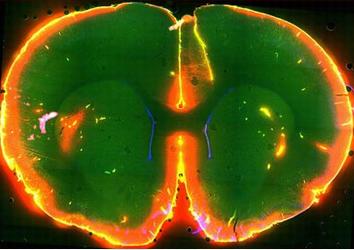

mouse brain

Scientists watched dye flow through the brain of a sleeping mouse. Photo courtesy of Nedergaard Lab, University of Rochester Medical Center)

Initially the researchers studied the system by injecting dye into the cerebrospinal fluid of mice and watching it flow through their brains while simultaneously monitoring electrical brain activity.

The dye flowed rapidly when the mice were unconscious, either asleep or anesthetized. In contrast, the dye barely flowed when the same mice were awake.